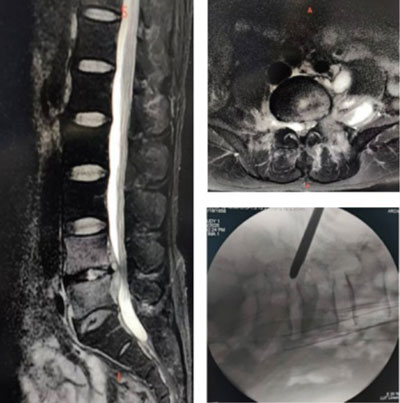

腰椎是脊柱结核最常见的发病部位,因此腰椎结核是常见的脊柱结核。腰椎结核主要造成骨质破坏和脓肿形成,导致脊柱稳定性丢失和神经功能障碍。本例患者椎管内脓肿形成,压迫神经根及硬脊膜,造成患者右足及右小腿麻木及疼痛。抗结核治疗1个月,右足及右小腿麻木及疼痛未见缓解。这种情况需要外科手术干预,以解除神经压迫,改善症状及挽救神经功能。

鉴于该患者目前的情况,治疗采取了微创手术方式,即椎间孔镜手术。在局麻下,切口约1cm,使用椎间孔镜直达锥管内,进行结核病灶清除及神经减压。微创手术的优点是手术创伤小、神经减压充分、手术时间短、术中出血少,且无需全麻,对身体影响小。患者术后即刻感觉右足及右小腿麻木及疼痛明显好转。